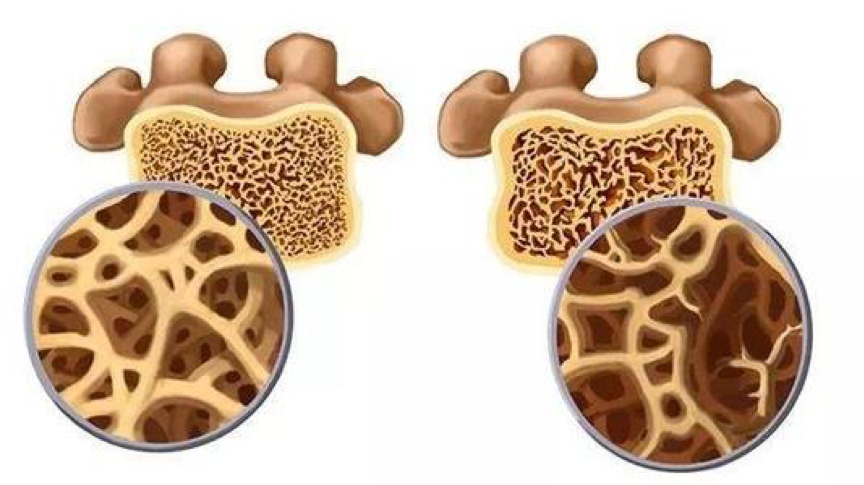

老年髋部骨折常见的有两种:一种是股骨颈骨折,一种是股骨转子间骨折或粗隆间骨折。随着寿命的延长,骨质开始变得疏松,肌肉开始萎缩,特别是绝经期后的妇女,情况更加严重。

基础治疗---抗骨质疏松

根据指南建议60岁以上的老年人,均应积极预防骨质疏松,正规的预防和治疗骨质疏松是非常必要的,除了日常补充钙剂,活性维生素D以外,户外晒太阳,合理锻炼也是必不可少的。